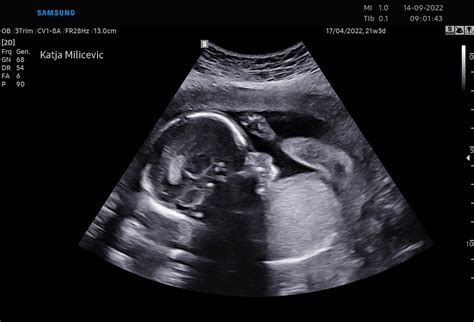

V tem tednu otrok že lahko odpira in zapira oči, ima redne intervale spanja in budnosti. Čeprav pljuča še niso popolnoma razvita, bi imel ob prezgodnjem rojstvu že manj zdravniških težav. Morda boste občutili hecno premikanje trebuha, ki ga povzroča otrokovo kolcanje, kar je povsem normalno. Otrok v maternici sedaj široko odpira oči, kar je vidno tudi na ultrazvoku. Razvija sposobnost uravnavanja telesne temperature, kostni mozeg pa je povsem dozorel in sam izdeluje rdeče krvničke. Otrok v maternici tudi lula in s tem proizvede do pol litra plodovnice dnevno.